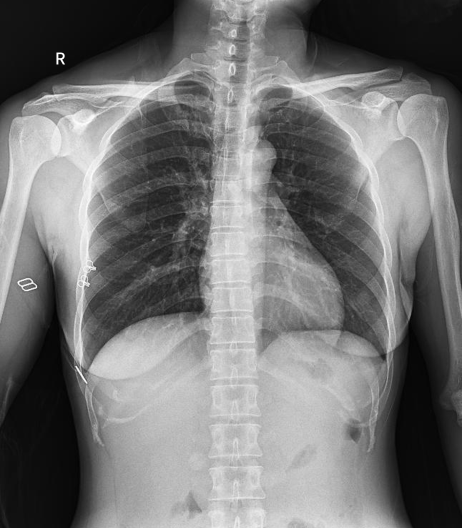

普利德醫(yī)療自主研發(fā)的新一代數(shù)字化X線透視攝影系統(tǒng),可應(yīng)用于DR攝影、數(shù)字透視、數(shù)字造影以及可視化精準(zhǔn)DR拍片等多種臨床X線檢查領(lǐng)域。

● 高效動(dòng)態(tài)平板技術(shù),圖像不會(huì)有幾何畸變,提供高分辨率和精確的圖像,為醫(yī)生臨床診斷提供精準(zhǔn)依據(jù);

● 最高幀速可達(dá)30幀/秒,動(dòng)態(tài)采集清晰流暢,避免漏診、誤診情況的發(fā)生;

● 在可視過(guò)程或回放過(guò)程中,如發(fā)現(xiàn)疑似病灶,可進(jìn)行毫秒級(jí)高清點(diǎn)片,隨時(shí)抓取單幀圖像,精準(zhǔn)捕抓病灶。